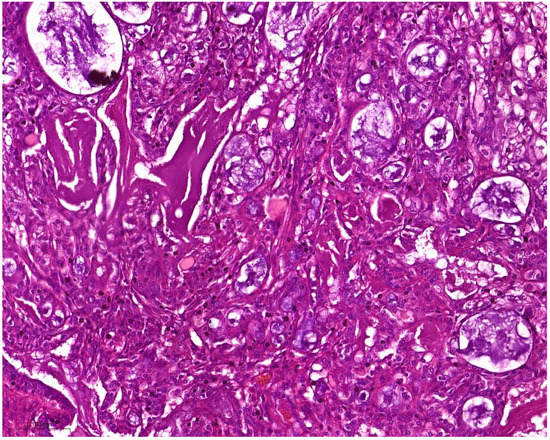

Conventional MEC was characterized by neoplastic squamous, mucinous, and intermediate components. The squamous component consisted of polygonal cells with eosinophilic cytoplasm and distinct cell borders, resembling squamous epithelial cells. The mucinous component comprised glandular structures filled with mucin-producing cells. The intermediate component consisted of cells with features between squamous and mucinous cells. These components varied in proportion within the tumor, leading to different histologic patterns. Clear cell MEC was characterized by the presence of clear cytoplasm within the tumor cells. The cytoplasm appeared optically clear due to the accumulation of glycogen or lipid droplets. This clear cell change was typically seen in the intermediate or mucus-secreting cells of MEC (Figure 1). Oncocytic MEC revealed a predominance of oncocytic cells within the tumor with granular eosinophilic cytoplasm. The oncocytic change involved both squamous and mucinous components of MEC. Warthin-like MEC exhibited histologic features reminiscent of Warthin tumor without abluminal oncocytic cells. The cystic spaces were filled with eosinophilic material resembling lymphoid stroma. These cystic spaces were surrounded by lymphoid tissue, with transition zones showing neoplastic and metaplastic squamoid and mucinous differentiation.

Figure 1. MEC with clear cell features. MEC architecture reveals a heterogeneous composition of mucin-secreting cells, epidermoid cells, and clear cells. Clear cells exhibit distinct transparent cytoplasm, lacking the typical granular or eosinophilic appearance seen in mucin-secreting and epidermoid cells. The nuclei of the clear cells are predominantly round or oval-shaped, exhibiting fine chromatin and prominent nucleoli. (H and E, magnification 20×).